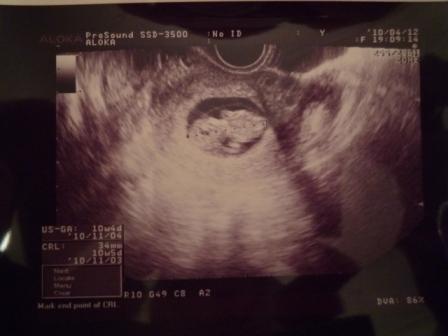

Én mindig csak az u.h-kat várom, de izgulok is miattuk nagyon.Én már olyan rég láttam a babánkat, több, mint 3 hete

Ági, gyönyörűséges a babád